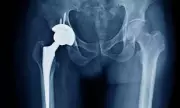

NHS Surgeries at Risk Due to Bone Cement Supply Crisis

Thousands of NHS hip and knee replacement surgeries could be delayed or cancelled due to a critical shortage of bone cement, caused by a packaging fault at a major supplier. The NHS is scrambling to find alternatives as patients face extended waits.